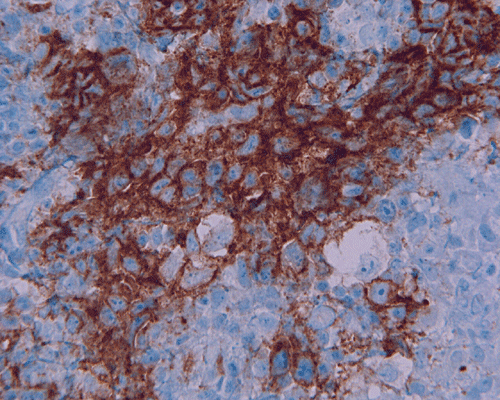

Paraffin sections: The entire volume of the tissue is made up of a granulomatous inflammation with poorly formed granuloma (Panel F, G, and H). The density of the lymphocytes is variable in different areas. In some areas, there is a rather intense lymphocytic infiltration accompanied by scant atypical cells with enlarged nulcei and prominent nucleoli (arrows in Panel I and J, Panel J is a higher magnification of Panel I). These atypical cells are quite easy to be missed. No microorganisms were identified by acid fast stain, PAS stain or GMS stain. The lymphocytes but not the atypical cells are positive for CD20 (Panel K) or CD3 (Panel L). The granulomatous background is strongly positive for CD68 (Panel M). Only rather faint positive staining for placental alkaline phosphatase (PLAP) is demonstrated and the interpretation is difficult as they are present in areas with crush artifact (Panel N). Many of the large, atypical cells are positive for CD117 (c-kit) (Panel O).

Immunohistochemically, the neoplastic cells show cytoplasmic membranous patten, sometimes diffuse cytoplasmic pattern, of staining for placental alkaline phosphatase (PLAP). Detection of c-kit (CD 117) in germinoma has been demonstrated and serves as a good diagnostic aid. Activating KIT mutations may contribute to tumorigenesis in germinoma 6, 7, 8. Syncytiotrophoblastic cells can be positive for human chorionic gonadotrophin (hCG). Occasional positive immunoreactivity for cytokeratin has been described and should not be taken as the sole evidence for embryonal carcinoma.

Mutation of c-kit gene at exon 11 (W557C) or 17 (D816V, D820V, and N822Y) were found in four germinomas (25.0%). To this date, no statistically significant difference in any clinicopathological factor was found between patients with or without mutations 8 but further studies is needed to explore the therapeutic potential of this finding.